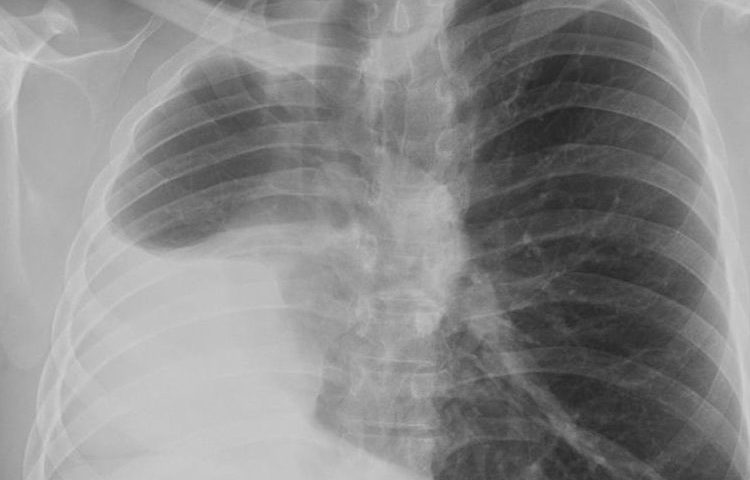

Аплазія легень у дітей та дорослих

Аплазія легень являє собою часткове відсутність даного органу. Аномалія вважається …